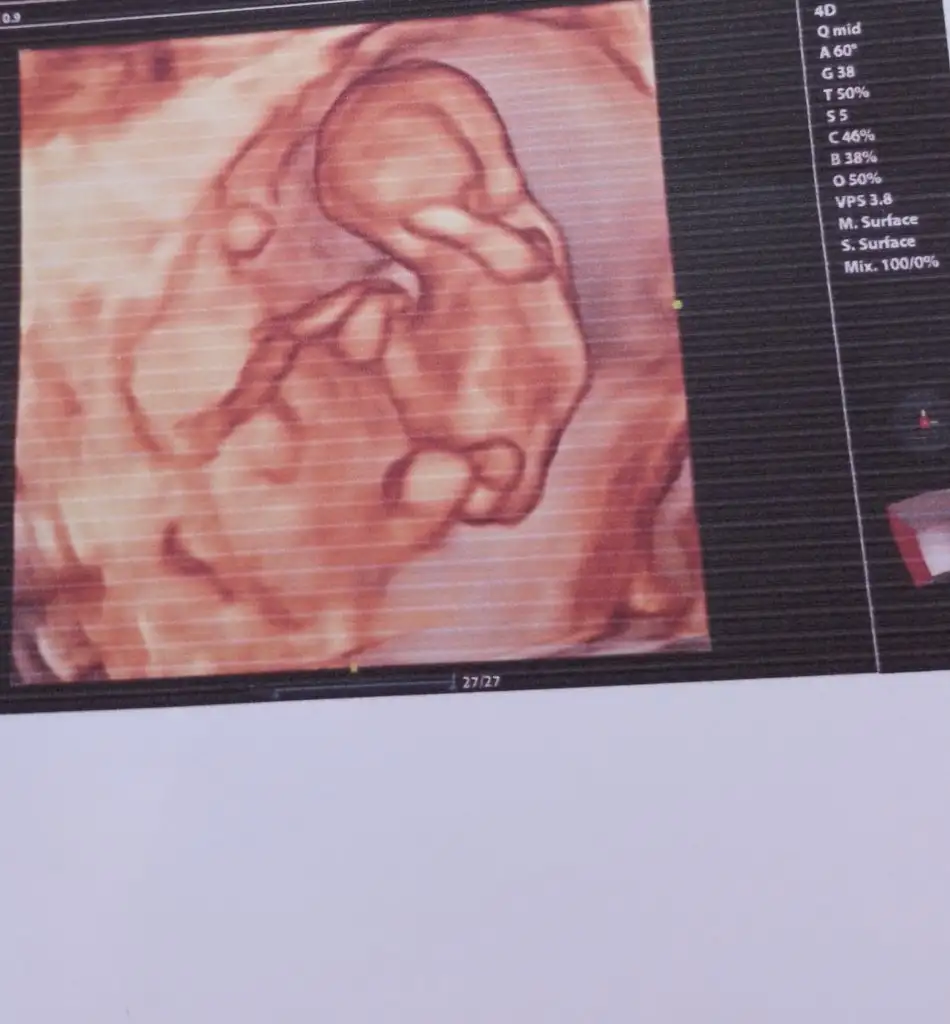

Merhaba ben de tahmin alabilir miyim? Tesekkurler:)

Eklentiler

• InCollage_20231118_134950662.webp

InCollage_20231118_134950662.webp

55,1 KB · Görüntüleme: 75

Arkadaşlar merhaba daha önce burada ultrason fotoğrafına bakıp cinsiyet tahmin edenleri görmüştüm benim içinde bi heyecan olur:) var mıdır tahmininiz normalde 12+4 üm ama ultrasonda 13 haftalık görünüyor